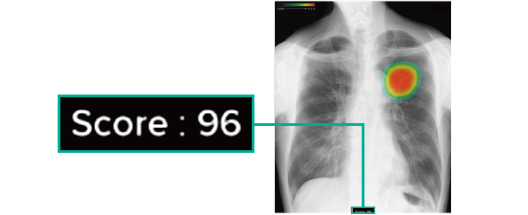

AI機能搭載の胸部X線画像診断ユニットEX-Mobile

AI機能搭載の「胸部X線画像病変検出ソフトウェア CXR-AID」は、レントゲンの画像の異常が疑われる範囲を解析しスコア化、ヒートマップで表示してくれるシステムです。 AIによる診断サポートで、短時間で精度の高い診断が可能となりました。

ヒートマップ機能

異常領域の解析を行い、解析結果の確信度に応じて赤くなるように表示されます。

スコア表示機能